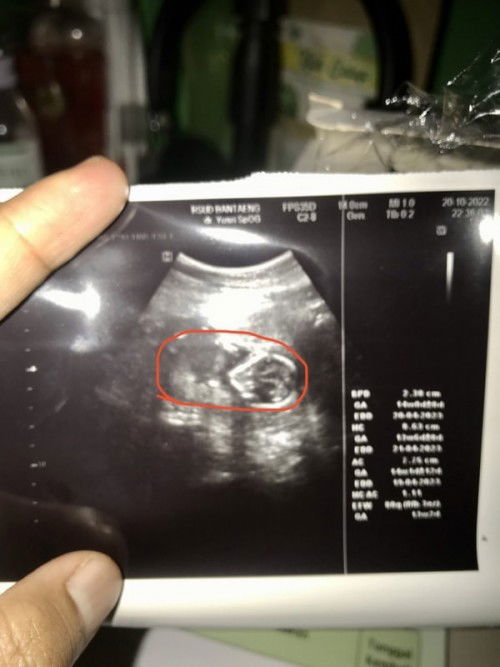

Hasil USG 14w. Kok aku lihatnya gak jelas ya? Apa krna kualitas alat usg nya??

Ada gak bunda yang punya foto usg 14w?? Oh ya. Yang dilingkari merah itu kata dokter janinnya

Đọc thêmposisi janin jg mempengaruhi usg sih bun. itu posisinya dr atas. biasanya mau ngukur diameter kepala. fotonya bunda ga fokus jd tulisan d kertas usg nya ga jelas. tp klo diameter kepala tulisannya yg BPD itu bun.

Tergantung alat USG yang digunakan bun .. 2D /3D/4D/5D ... sama dengan hp ada yg kameranya bagus ada kameranya yang kurang bagus burem .. itu yang di tangkap bagian lingkar kepalanya bun 😇

saya ngelihatnya jelas kok bund.. itu yang bentuknya seperti telur adalah kepala janinnya.. tangan sama kakinya ngangkat.. wajah janin lihatnya ke arah atas ...

Harusnya si udah jelas ya bun.. itu janinnya kaya tengkurep ya bun kalau saya perhatiin.. saya kemarin usg 10/11week dah keliatan seperti ini bunn..